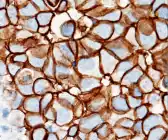

Immunohistochemistry

By immunohistochemistry, the sample is given a score based on the cell membrane staining pattern.

| Score[43][44] | Pattern[45] | Status[43][44] |

|---|---|---|

| 0 | Either:[45]

|

HER2 negative (not present) |

| 1+ | Incomplete membrane staining that is faint or barely perceptible and within >10% of the invasive tumor cells.[45] | |

| 2+ | Weak to moderate complete membrane staining observed in >10% of tumor cells.[45] | Borderline/Equivocal |

| 3+ | Circumferential membrane staining that is complete, intense, and in >10% of tumor cells.[45] | HER2 positive |

Micrographs showing each score:[46]

-

0

0 -

1+

1+ -

2+

2+ -

3+

3+